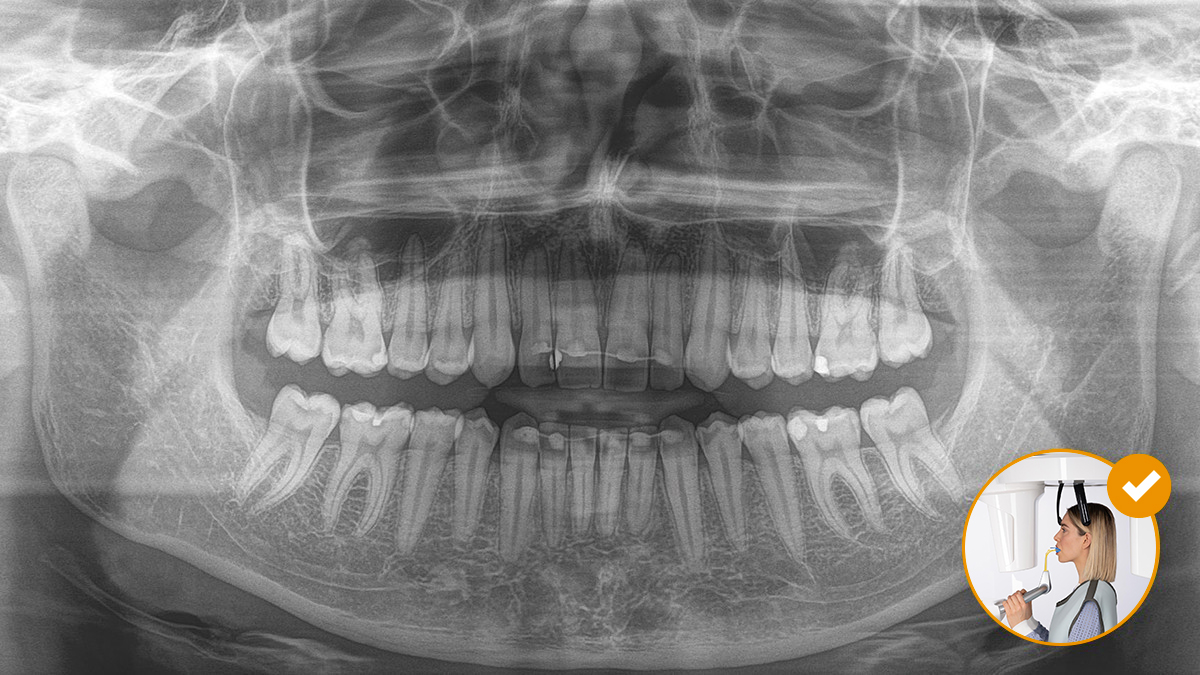

Il corretto posizionamento del paziente porta a un’elevata qualità dell’immagine per supportare una diagnosi accurata e facilita e migliora l’esperienza del paziente.

Questo è il nostro concetto a 10 punti per facilitare il posizionamento del paziente e l’acquisizione di immagini radiografiche. Si tratta principalmente di due cose: alta qualità dell’immagine e comfort per il paziente e l’assistente.

Il funzionamento del morso occlusale non potrebbe essere più semplice. Con l’aiuto dei simboli e dei colori sul display del dispositivo radiografico, i medici hanno tutte le informazioni necessarie per una regolazione ottimale del dispositivo. Le frecce illuminate indicano in quale direzione l’unità deve essere spostata per ottenere l’inclinazione ideale della testa. Il dispositivo si arresta automaticamente una volta raggiunta la posizione corretta.